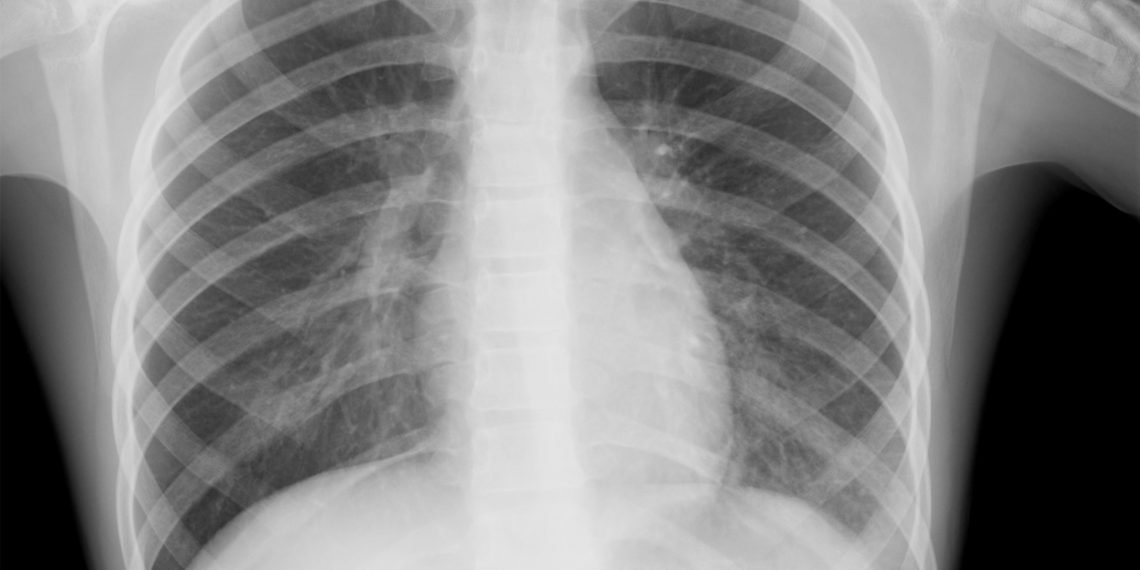

Зазначається, що 5 квітня в стаціонарні відділення лікарні поступив 74-річний чоловік з діагнозом двобічна позагоспітальна пневмонія. Хворого одразу госпіталізували у реанімаційне відділення. На жаль, врятувати його не вдалося: чоловік помер увечері того ж дня.

Дослідження на експрес-тест, який провели в Любомлі, та аналіз на полімеразно-ланцюгову реакцію ( ПЛР-дослідження), яку провели у Луцьку в обласному лабораторному центрі того ж дня, виявився негативним.